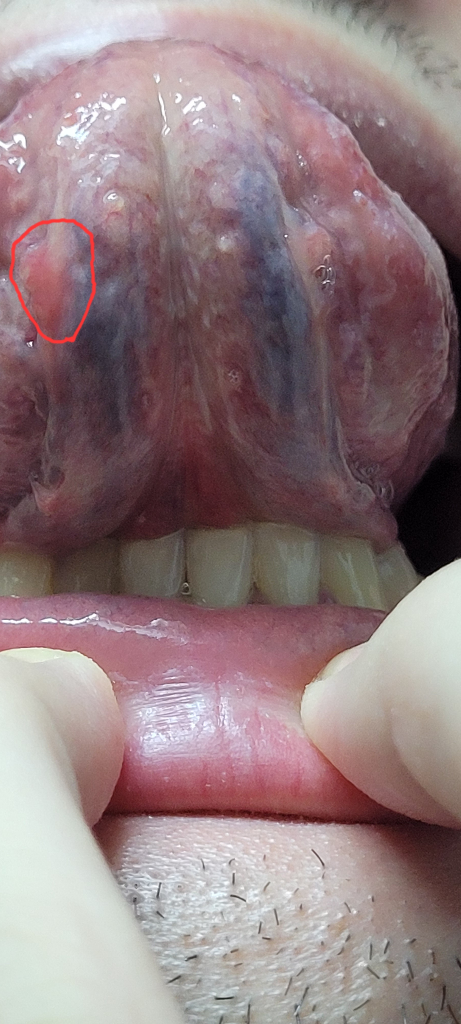

이거 구내염인가요 아니면 구강암인가요?

제가 한 몇주전부터 입이 아픈데 여길 만지면 팔랑거

리는 느낌과 통증이 있습니다.

이거 구강암인가요?

딱딱하지 않고 펄렁거리며 움직입니다.

• 사진의 소견을 통해서 구강암 여부를 판단할 수 없습니다. 구내염은 궤양성 병변이 나타나는 질환이기 때문에 구내염은 아니며, 해당 종물이 양성인지 악성인지 여부는 조직 검사를 통해서 감별이 가능하겠습니다. 이비인후과에서 진료 및 정밀 검사를 받아보시길 권고드립니다.